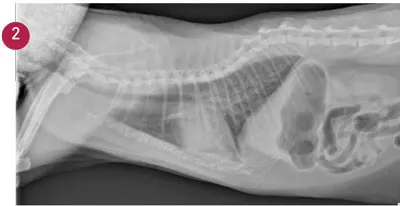

FIGURE 1

Echocardiogram of 10-year-old spayed female golden retriever with pericardial effusion and cardiac tamponade. An elevated cTnI increases the likelihood of neoplasia when a mass cannot be visualized on echocardiography.